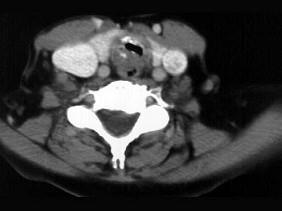

问题 男性,50岁,声音嘶哑近一年,近来感呼吸困难,CT扫描如图所示,请选择正确的描述和结论 ( )

选项 A、考虑为喉气管淀粉样变性 B、考虑气管结核 C、气管后方见软组织肿块 D、肿块内可见致密钙化影 E、喉、气管壁增厚

答案 ACDE